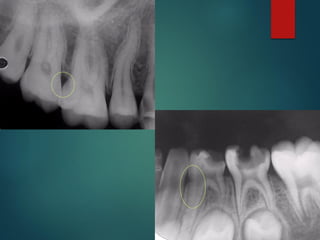

Clasificación Radiográfica

De Las Caries

 Incipiente de esmalte

 De esmalte

 Dentinaria superficial

 Dentinaria profunda

 Sobreproyectada en cámara pulpar

 Penetrante